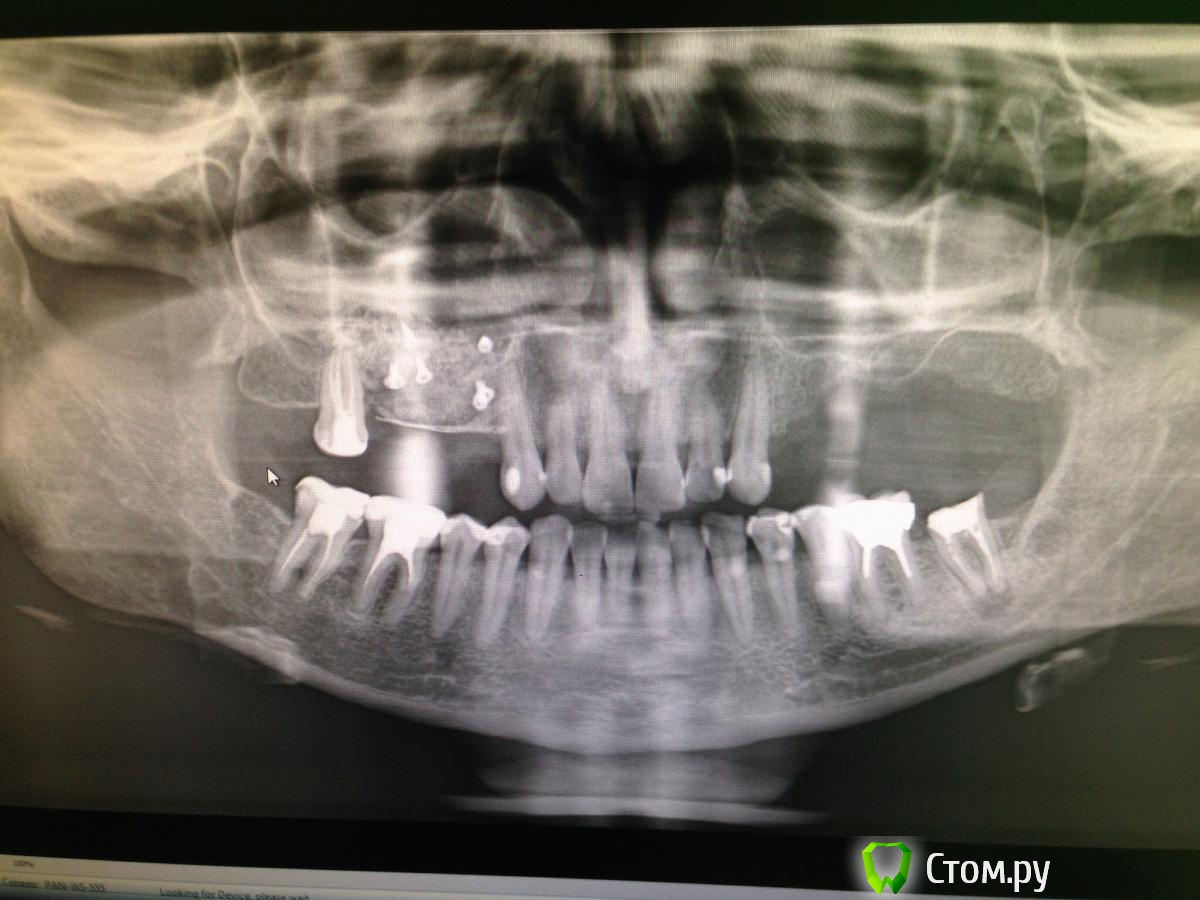

АнтонТЛТ Опубликовано 22 июня, 2014 Поделиться Опубликовано 22 июня, 2014 (изменено) Выложи ОПТГ, на ней будет понятнее нужно ли вертикалить Как мне кажется ниче там не нужно кроме синуса.Ну или выстави срез, чтобы попадал дистальный край альвеолярного отростка Изменено 22 июня, 2014 пользователем АнтонТЛТ Ссылка на комментарий

diesel87 Опубликовано 22 июня, 2014 Автор Поделиться Опубликовано 22 июня, 2014 Ссылка на комментарий